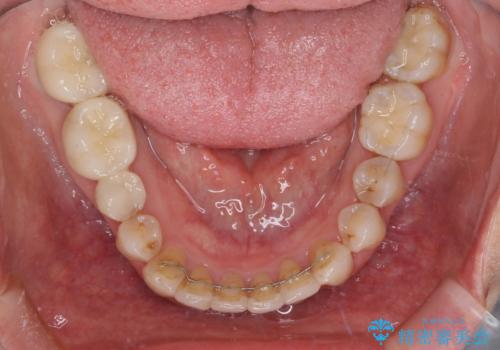

- 前歯の歯並びやむし歯治療の跡、奥歯の銀歯を気にして来院された患者様です。

インビザラインによる矯正治療の後に虫歯や銀歯をセラミックにて補綴することとしました。

前歯のむし歯治療の跡や奥歯の目立つ銀歯がなくなり、明るい口元になりました。